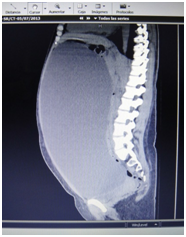

Female, thin, good oral mucosa hydration, limited moves to breathe, no cardiac problems. Abdominal wall prominent, peristaltic sound only heard in upper left side, diffuse mate noise in all abdominal cavity at the percussion exploration. Laboratories: Hb 10g/dl, Hto 30 WBC 10,300. N 56% Plaq 230,000 Glucose 89 mg/dL Na 135 mEq K 4mEq Cl105mEq. Axial Tomography (Figure 2 and Figure 3): shows a very big intraabdominal homogeneous mass, from de left ovarian pulling all organs to superior left abdominal quadrant

Figure 3 Laeral Axial Tomography shows Giant Cyst Ovarian all abdominal cavity ocuped.